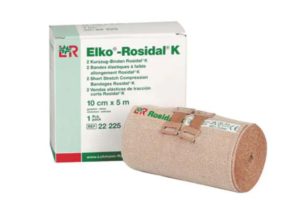

Korte rek zwachtels worden gebruikt voor het behandelen van oedeem.

Deze zorgen voor een hoge werkdruk en een lage rustdruk op het ingezwachtelde ledemaat, zodat de zwachtel ook ’s nachts kan blijven zitten.

De korte of lang rek zwachtel wordt vaak vastgezet met een stuk tape. Er zijn ook klemmetjes waarmee het vastgezet kan worden, maar pas hiermee op dat jij jezelf hiermee niet verwond en kans loopt op wondroos. Tevens kan er ook gebruik gemaakt worden van buisverband om alles goed op zijn plek te houden en om afglijden te voorkomen.